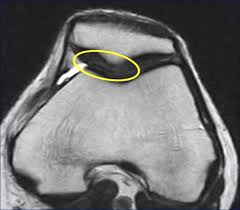

PATELOFEMORAL

S. PATELOFEMORAL